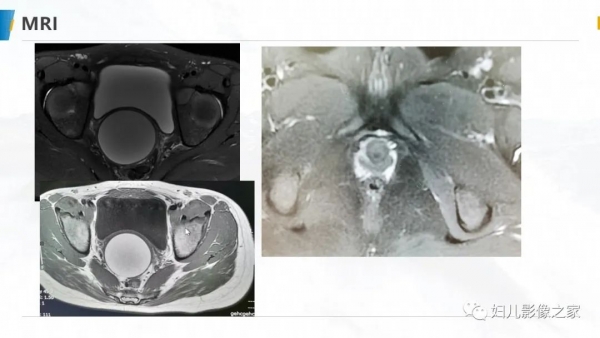

病例1

女,10岁,以“间断下腹痛7天”为主诉入院。入院查体:生命体征平稳, 心肺听诊无异常,腹软,肝脾未及,余无明显异常。

专科检查:外阴发育尚可,处女膜开口较小,棉签探入约4cm,无膨 隆,肛诊:子宫、宫颈膨隆,最低处距处女膜约4cm。

辅助检查:彩超(县中医院,2021-10-08):子宫体积增大,子 宫肌层变薄,内膜线消失,宫腔扩张,子宫颈管扩张,内充满大量液 性暗区,呈密集点状,阴道未见明显扩张。提示:1.胆囊内强回声2.胆 囊壁毛糙3.考虑处女膜闭锁。